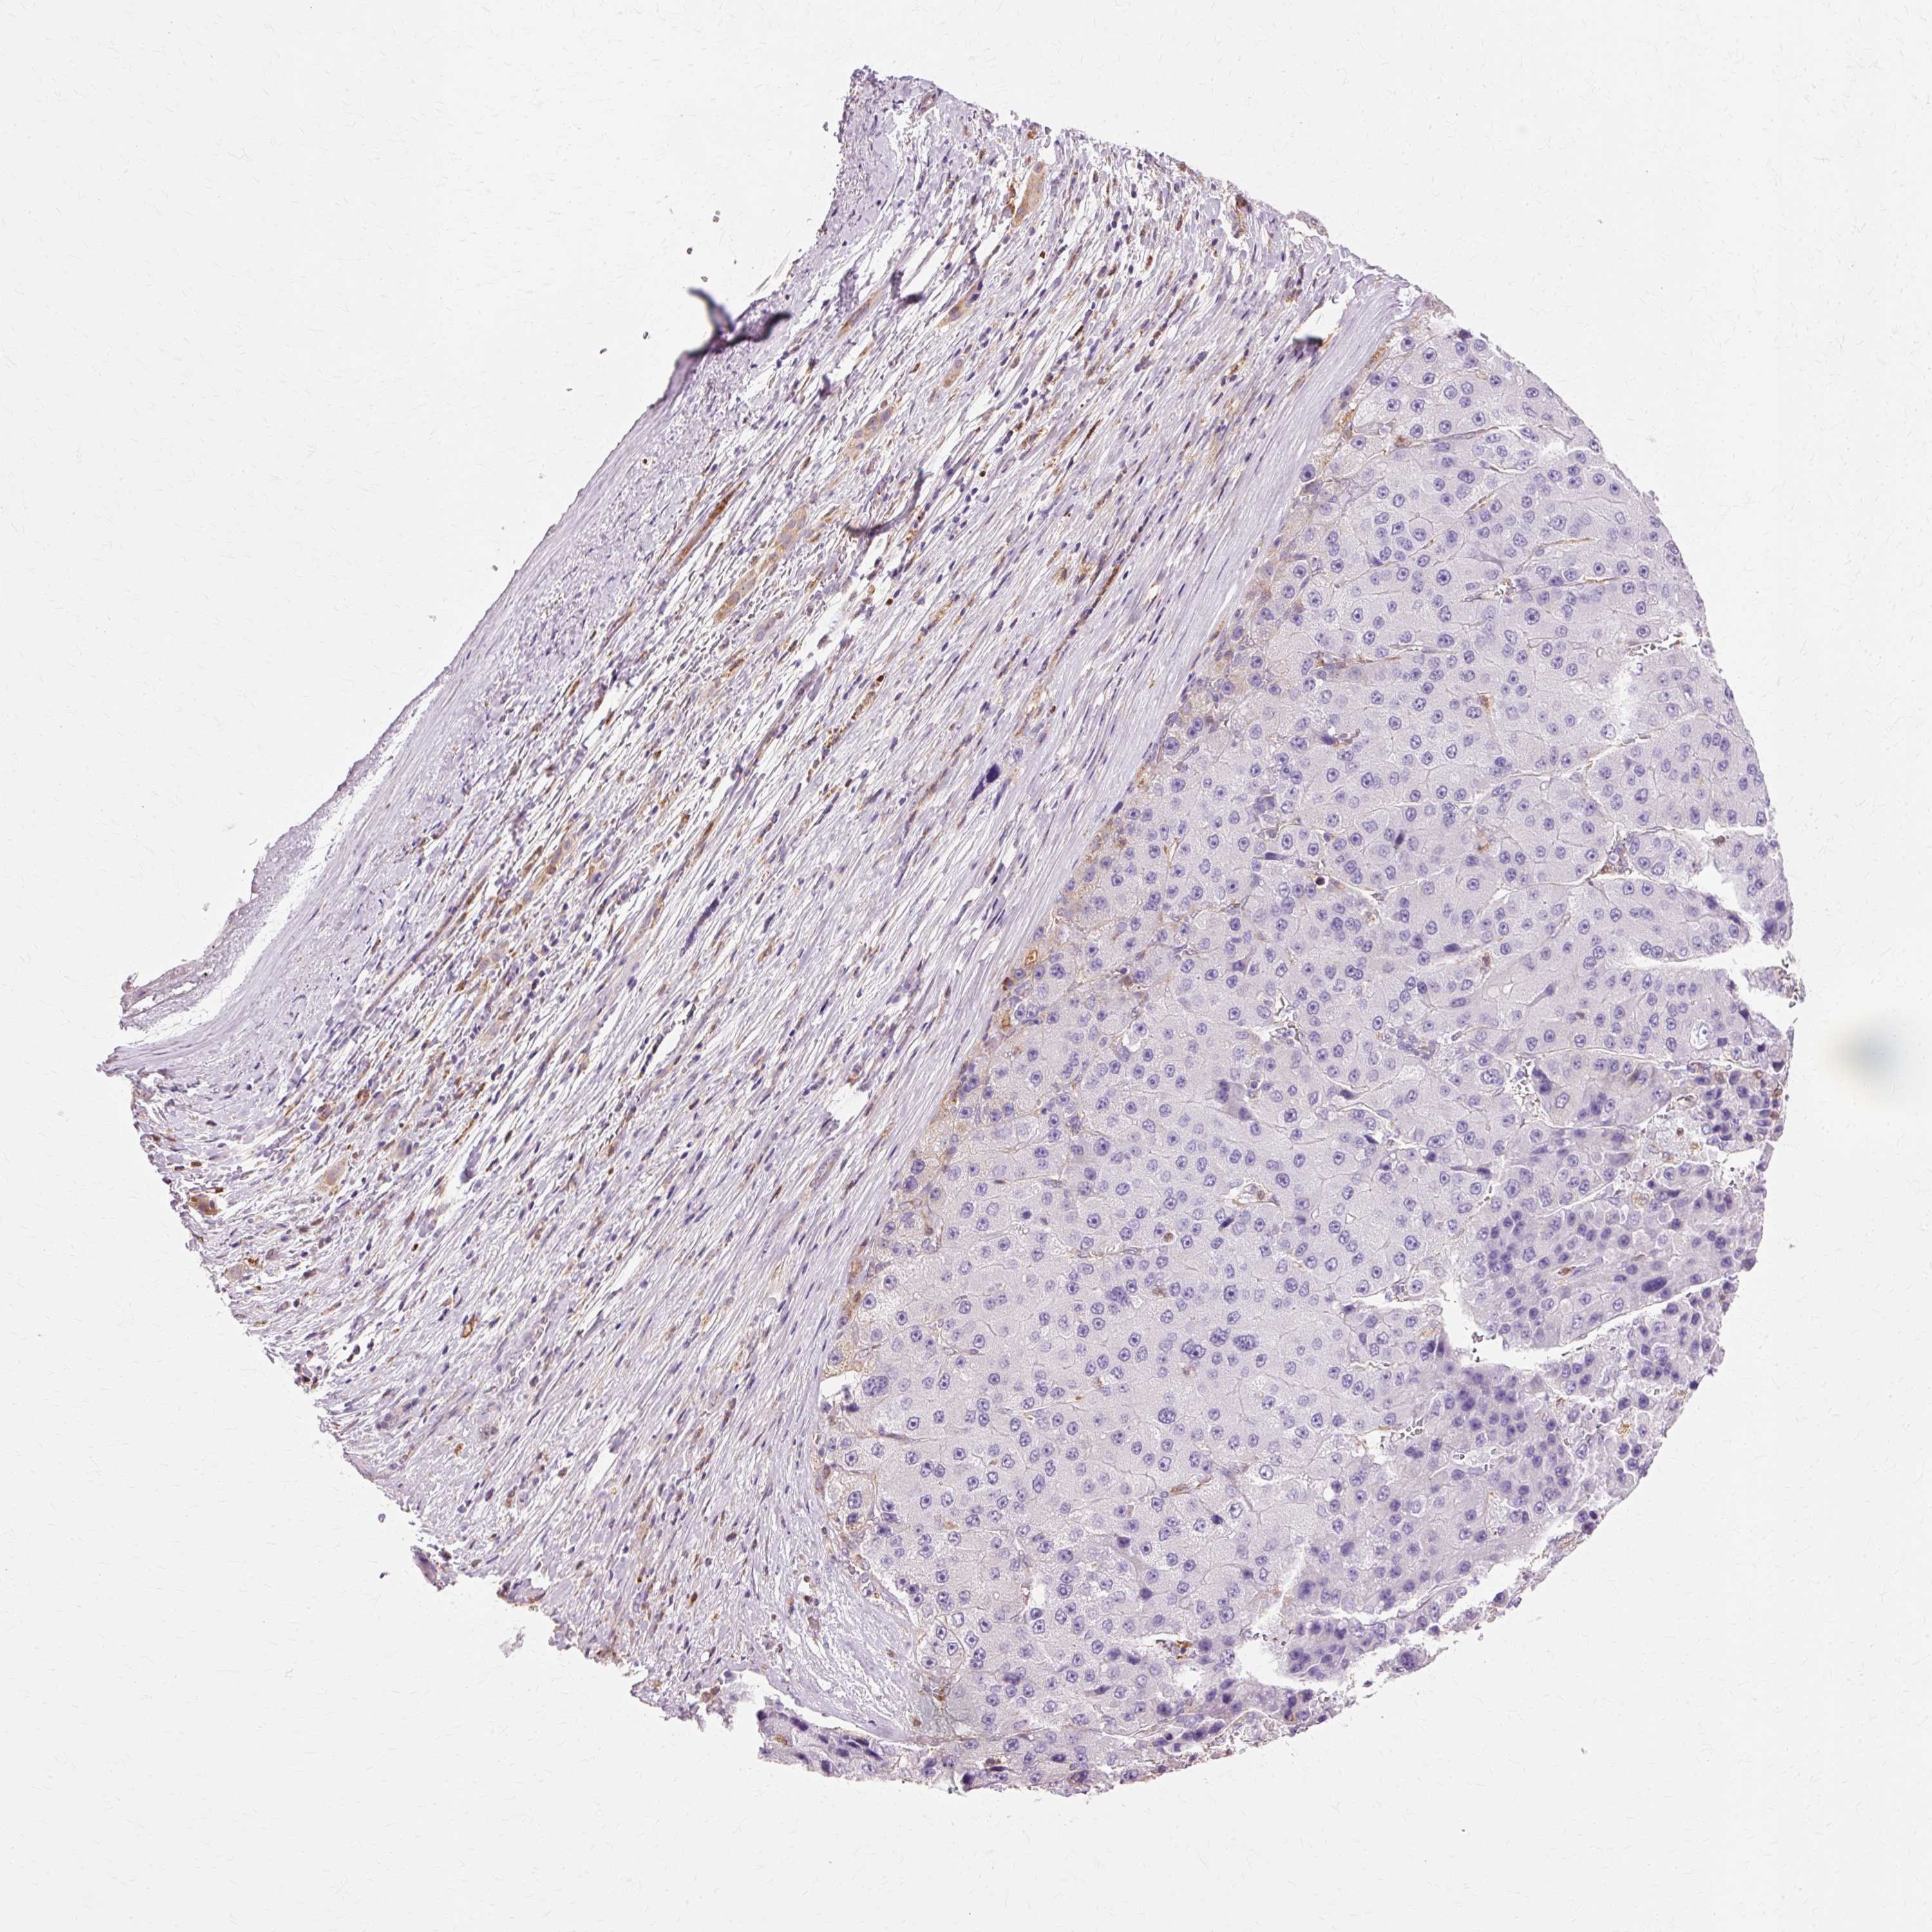

LIVER CANCER - Protein expressioni

A mouse-over function shows sample information and annotation data. Click on an image to view it in a full screen mode. Samples can be filtered based on level of antibody staining by selecting one or several of the following categories: high, medium, low and not detected. The assay and annotation is described here.

Note that samples used for immunohistochemistry by the Human Protein Atlas do not correspond to samples in the TCGA dataset.

Antibody stainingi

Antibody staining in the annotated cell types in the current human tissue is reported as not detected, low, medium, or high, based on conventional immunohistochemistry profiling in selected tissues. This score is based on the combination of the staining intensity and fraction of stained cells.

Each image is clickable and will lead to virtual microscopy that enables deeper exploration of all samples and also displays staining intensity scores, fraction scores and subcellular localization as well as patient and tissue information for each sample.

Antibody HPA044758

Antibody CAB011582

Staining

High

Medium

Low

Not detected

Intensity

Strong

Moderate

Weak

Negative

Quantity

>75%

75%-25%

<25%

None

Location

Nuclear

Cytoplasmic/membranous

Cytoplasmic/membranous,nuclear

Cholangiocarcinoma

Carcinoma, Hepatocellular, NOS